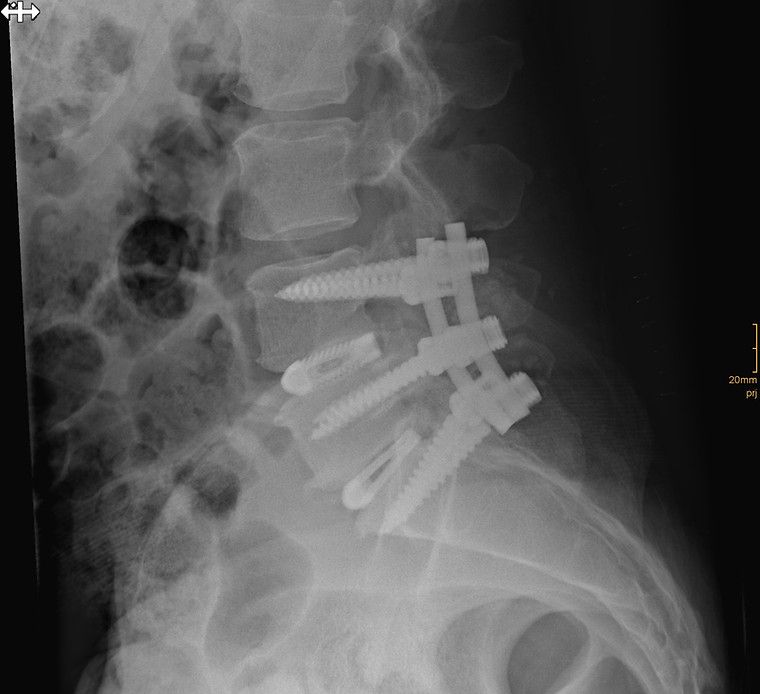

Als Facharzt für Orthopädie lag mein Schwerpunkt als Oberarzt im Wirbelsäulenteam des AKH Wien von 2019 bis 2024 auf der operativen Versorgung von Erkrankungen der Wirbelsäule. In den vergangenen Jahren habe ich viele hundert Wirbelsäulenoperationen durchgeführt – von mikrochirurgischen Eingriffen bis hin zu minimalinvasiven rekonstruktiven Verfahren. Dank meiner langjährigen Erfahrung verfüge ich über besondere Expertise in Bandscheibenoperationen, Dekompressionen sowie in der chirurgischen Behandlung schwerer Wirbelsäulenpathologien. Diese Eingriffe erfordern höchste Präzision, Sorgfalt und ein tiefes Verständnis der individuellen Krankheitsbilder. Besonders wichtig ist mir dabei, Sie umfassend zu beraten und gemeinsam mit Ihnen die für Sie beste Therapieentscheidung zu treffen. Ich nehme mir ausreichend Zeit für Ihre Fragen und sorge dafür, dass Sie sich medizinisch wie menschlich gut aufgehoben fühlen.

Es werden mikrochirurgische Bandscheibenoperationen und Dekompressionen durchgeführt.

Rekonstruktive Wirbelsäulenchirurgie

Wirbelsäulenpathologien werden durch minimalinvasive rekonstruktive Eingriffe versorgt.